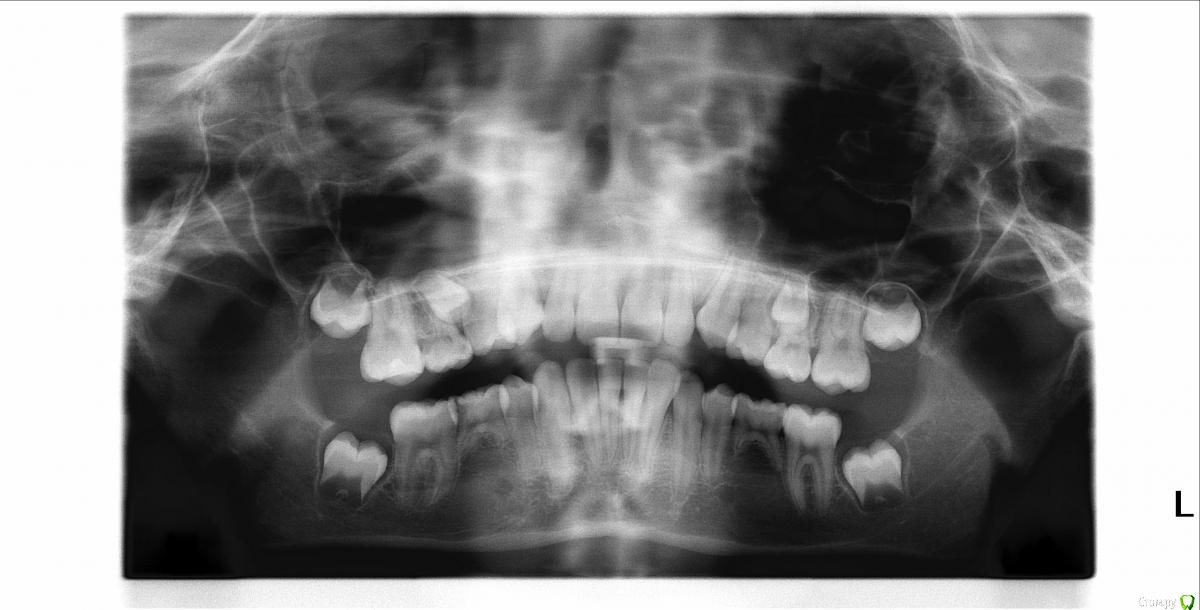

FeoKat Опубликовано 2 марта, 2016 Поделиться Опубликовано 2 марта, 2016 Здравствуйте,Очень нужен совет.Ребенок, 11 лет, верхние и нижние пятерки молочные, нет зачатков нижних 5ок, верхние есть, но зачаток правой 5ки лежит боком, 7ки еще не прорезались, зачатков 8ок нет.Планируем одеть брекеты.Предлагается 3 варианта:Вариант 1. вырывать все молочные 5ки, ставить брекеты, на верхней челюсти ждать когда полезут коренные 5ки, корректировать направление роста, на нижней двигать 6ки к 4кам.Вариант 2. вариант 1 + вырывать зачатки верхних коренных 5ок, чтобы впоследствии было правильное смыкание.Вариант 3. вырывать все молочные5ки, на нижней готовить место под импланты. Панорамный рентген в аттаче.Чтобы вы посоветовали и какую именно брекет систему (сейчас планируется DymonClear ВЧ3х3, НЧ3х3) Ссылка на комментарий

Brigita Опубликовано 9 марта, 2016 Поделиться Опубликовано 9 марта, 2016 (изменено) Имплантация внизу лучший вариант, но это будет в 18 лет, и по снимку не понятно состояние молочных 5к-затемнение области под ними.Что говорит терапевт- их можно пока оставить пока?На верху корни постоянных еще не сформированы, удаление молочных зубов не приведет к их прорезыванию. Вытягивать их тоже пока нельзя. Покажите еще снимки-трг и фото зубов, лицо в профиль и анфас, чтобы понимать, есть еще проблемы, кроме 5к. Изменено 9 марта, 2016 пользователем Brigita Ссылка на комментарий